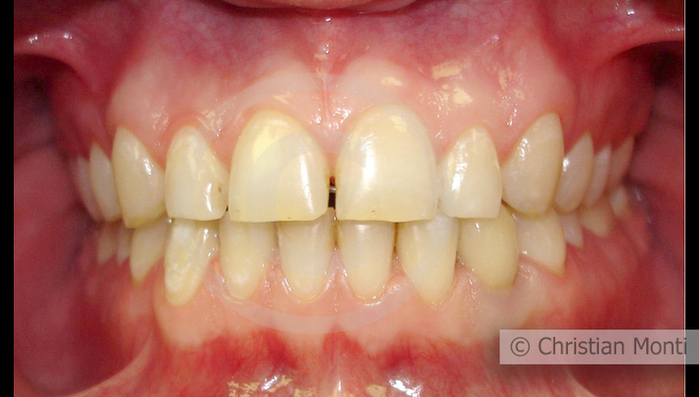

EDENTULIA SINGOLA

Impianto in sostituzione di un canino deciduo